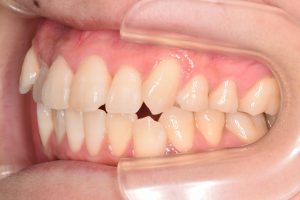

左側

両側の犬歯が咬みあっていないので

奥歯にとても負担のかかる咬合状態でした。

犬歯を咬合に参加させることで

奥歯に負担が掛からなくなります。

(犬歯誘導)